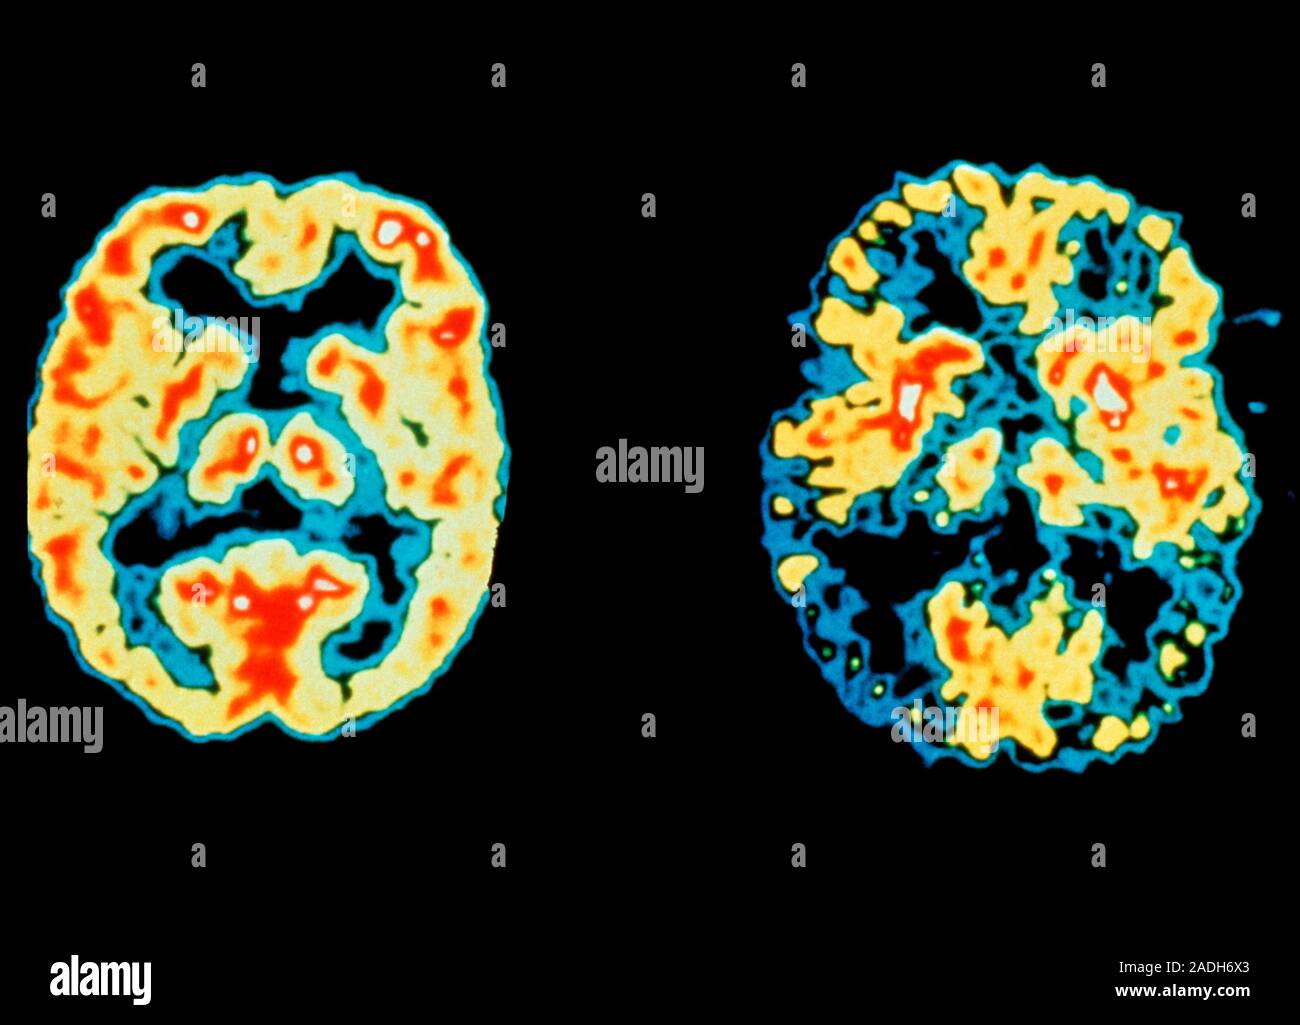

All you need to know about brain scans and dementia Alzheimer's

From www.sciencephoto.com

Dementia, MRI scans Stock Image M140/0435 Science Photo Library Will A Ct Scan Show Alzheimer S First, the scan helps your doctor rule out conditions. Web the goal of a head ct scan for alzheimer’s disease is twofold. Web while they may show shrinkage of some brain regions associated with alzheimer's disease, mri scans also rule out other conditions. They are useful for ruling out. Web alzheimer’s symptoms and diagnosis. Types of biomarkers and tests. Web. Will A Ct Scan Show Alzheimer S.